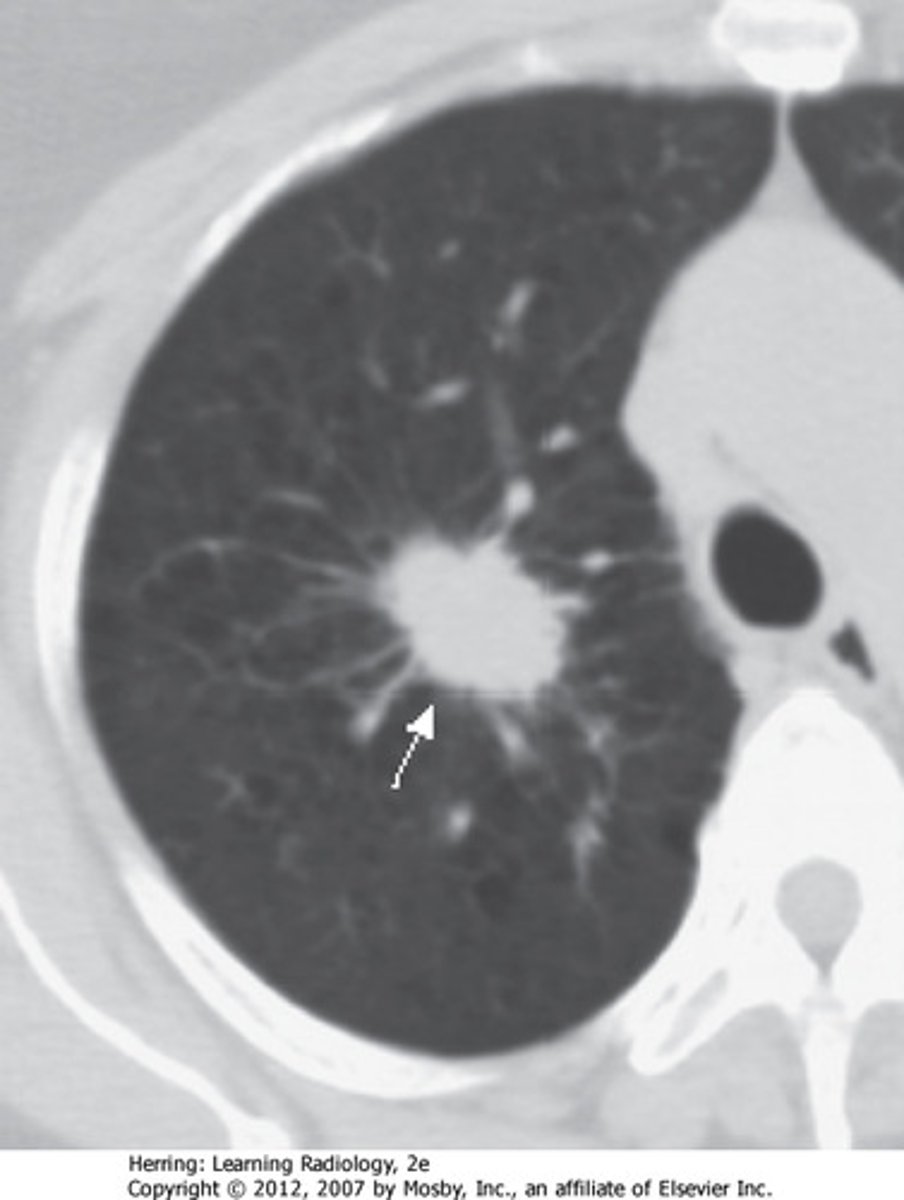

pulmonary neoplasm

pertaining to (in) the lung, new growth (tumor)